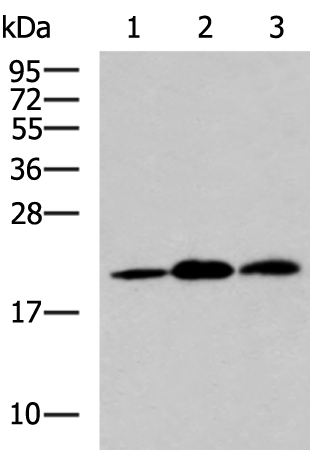

分类: 科研抗体货号: P11178别名: AR; ADR; ALR2; ALDR1应用: WB,IHC反应种属: Human

分类: 科研抗体货号: P11177别名: ALR; ARM; DD3; ALDR1应用: WB,IHC反应种属: Human, Mouse, Rat